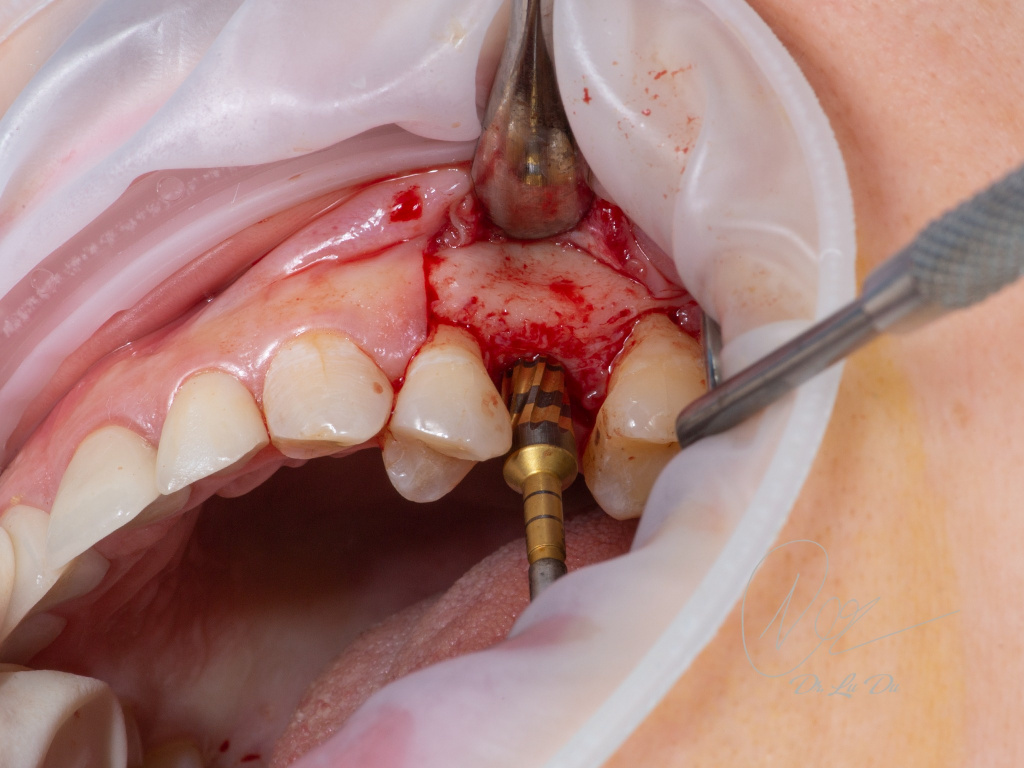

Имплантация AnyRidge с двусторонним закрытым синус-лифтингом.

Осложнения: правосторонний гайморит.

Кейс MINEC: Dr Lu Du